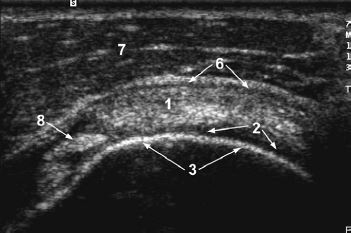

1. rotator cuff

2. cartilage

3. humeral head

4. anatomic neck

5. greater tuberosity

6. subdeltoid bursa

7. deltoid muscle

8. biceps tendon

The intra-articular portion of the biceps tendon

separates the subscapularis and the supraspinatus.